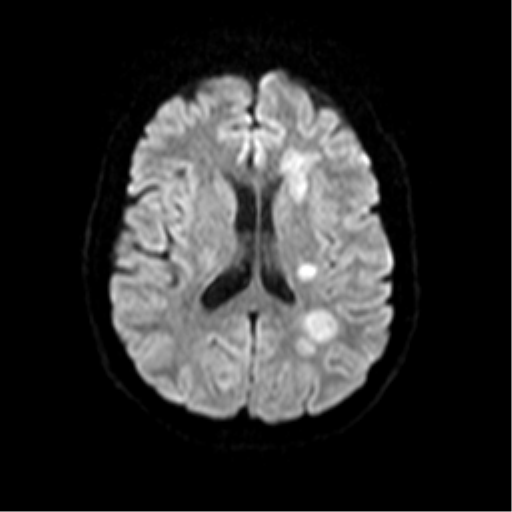

• DWI - peripheral restricted diffusion but not centrally

DWI showing peripheral restriction without central restriction

Peripehral open ring restriction on DWI not always seen as evidenced below